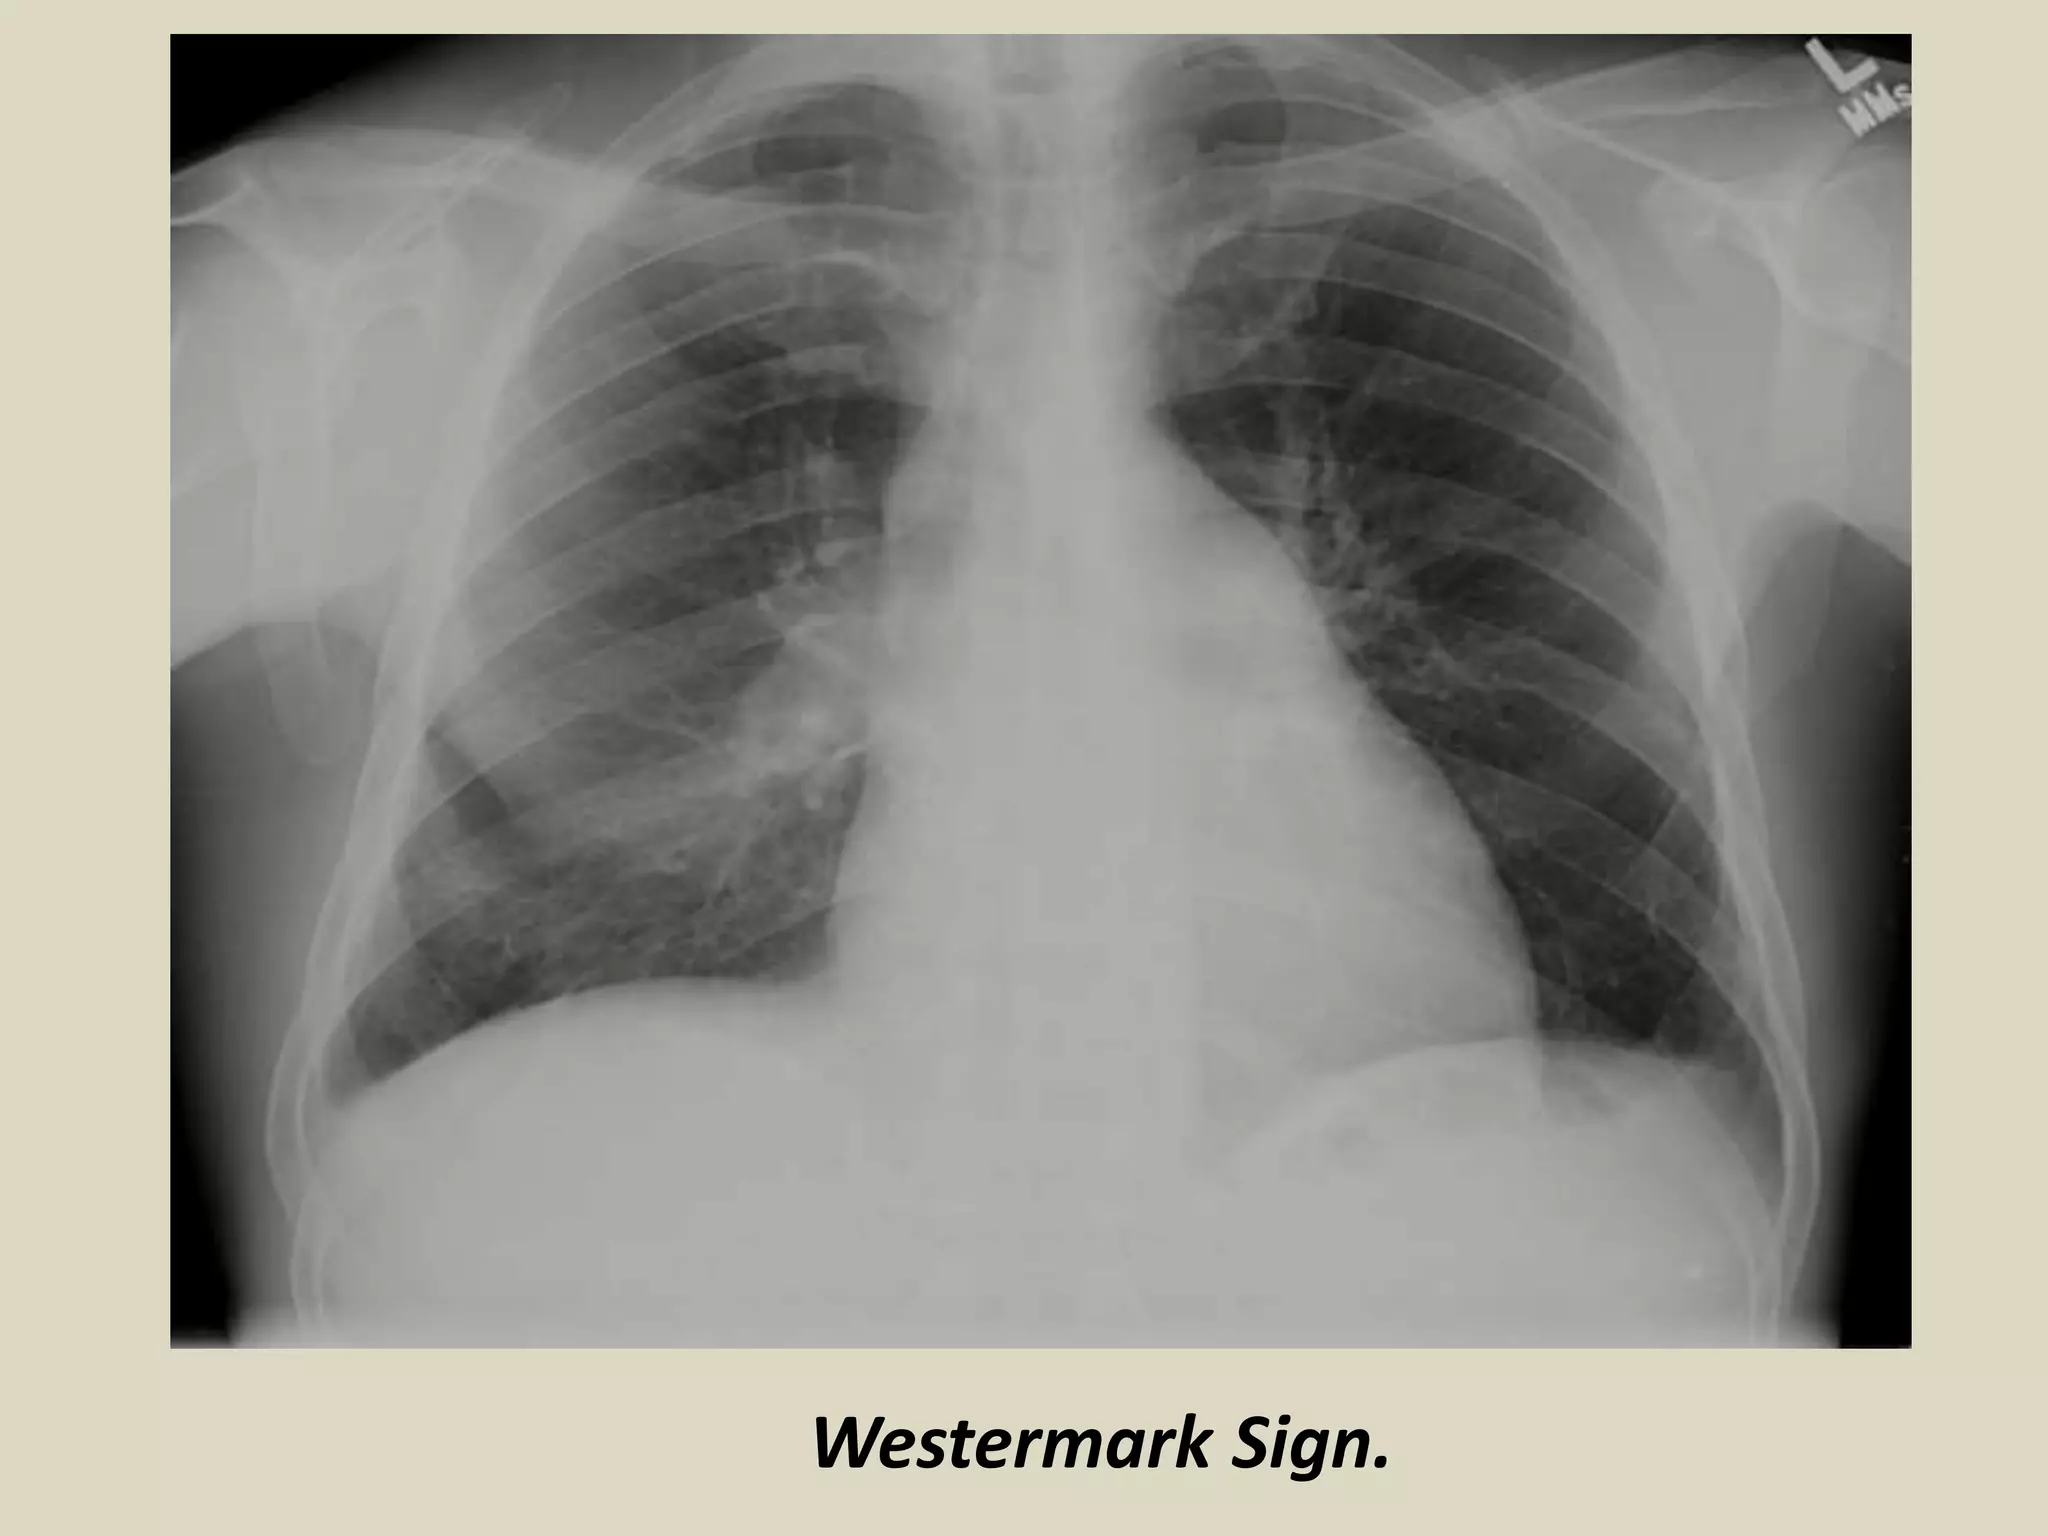

WESTERMARK SIGN

Described by Neil Westermarck in 1938

Chest radiograph and CT show increased lucency or

hypoattenuation

Typically signifies either occlusion of a larger

lobar/segmental artery or widespread small vessel

occlusion

Represents oligemia distal to PE; seen only in 2% of

patients

Sign results from combination of dilatation

pulmonary arteries proximal embolus and collapse

of distal vasculature

Low sensitivity 11%, high specificity 92%

WESTERMARK SIGN. Chest radiograph and schematic drawing.

Westermark Sign.

WESTERMARK SIGN Described byNeil Westermarck in 1938 Chest radiograph and CT show increased lucency or hypoattenuation Typically signifies either occlusion of a larger lobar/segmental artery or widespread small vessel occlusion Represents oligemia distal to PE; seen only in 2% of patients Sign results from combination of dilatation pulmonary arteries proximal embolus and collapse of distal vasculature Low sensitivity 11%, high specificity 92%

WESTERMARK SIGN. Chestradiograph and schematic drawing.